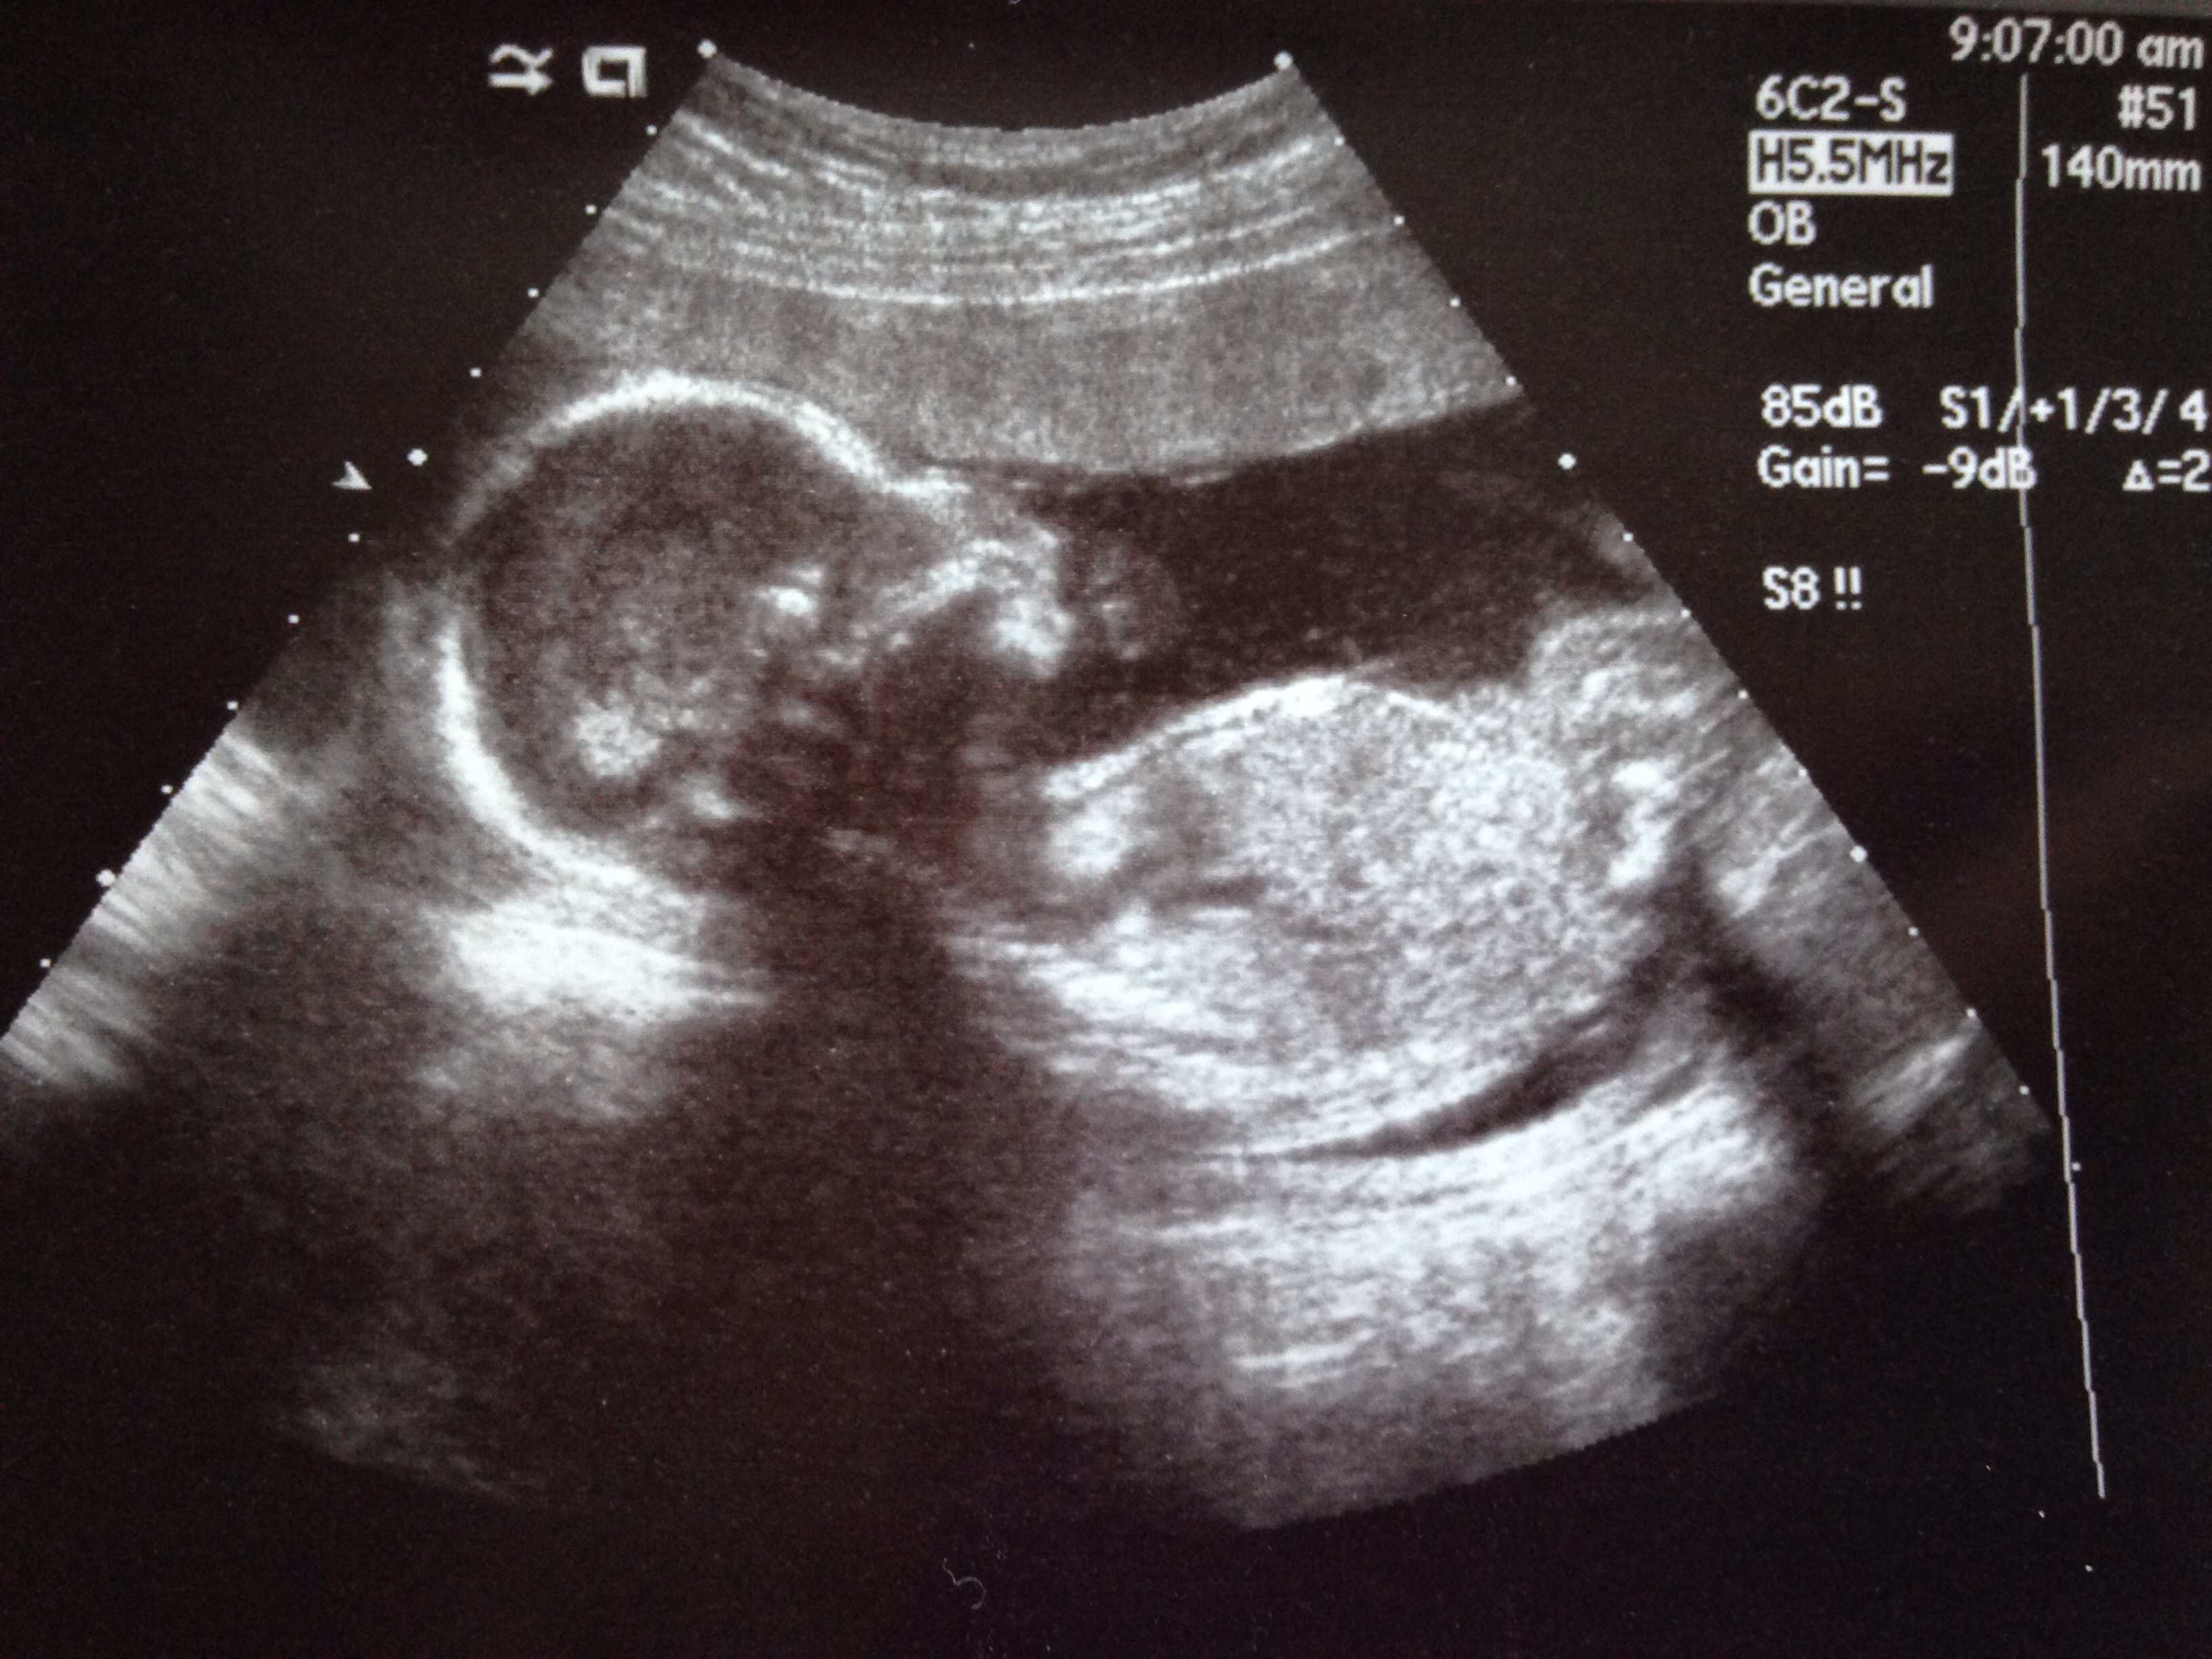

1st u/s pic at about 13w

2nd at 21w. Team blue! (Again!)